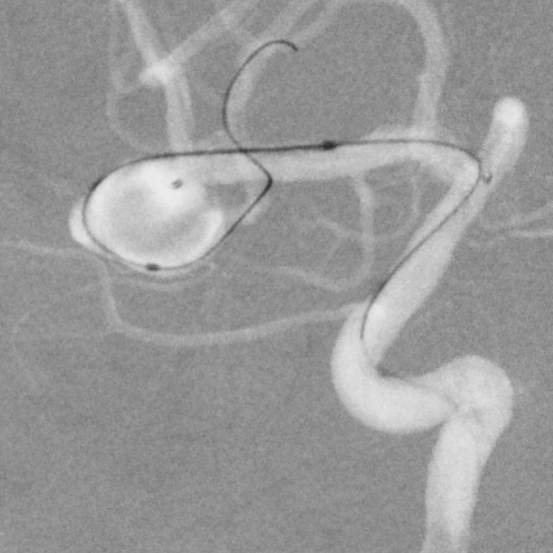

粗大分支从破裂瘤体上发出来,急性期能单纯致密栓塞吗?

病史:中年女性,新冠感染,颅内动脉瘤破裂,Hunt-Hess 4级

最终,动脉瘤瘤体致密栓塞,各个分支保留良好